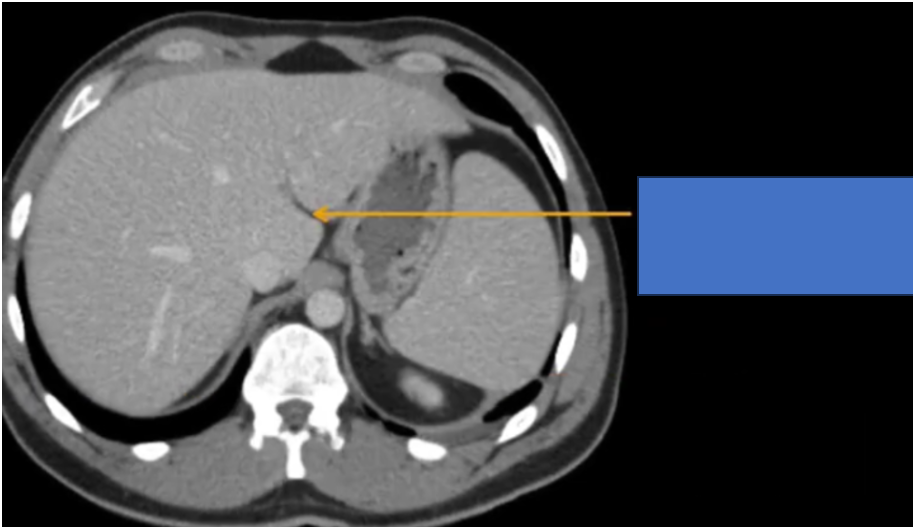

cq trong hình ?